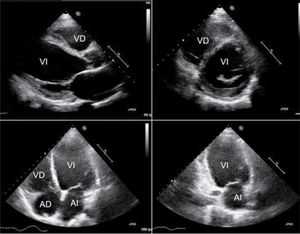

La miocardiopatía dilatada (MCD) es una entidad clínica caracterizada por dilatación ventricular izquierda o biventricular y disfunción sistólica, en ausencia de enfermedades de carga o isquémicas suficientes para justificarla. Su etiología es heterogénea e incluye factores genéticos, infecciosos, tóxicos, metabólicos y autoinmunes. Clínicamente, pueden observarse desde formas asintomáticas hasta situaciones de insuficiencia cardíaca avanzada, arritmias o muerte súbita. El diagnóstico se basa en la integración de hallazgos clínicos, de imagen y biomarcadores, destacando el papel de la resonancia magnética cardíaca y las pruebas genéticas en la evaluación etiológica y pronóstica. El tratamiento incluye terapia médica con inhibidores del sistema renina-angiotensina-aldosterona (SRAA), bloqueadores beta-adrenérgicos, antagonistas del receptor de mineralocorticoides (ARM) e inhibidores del cotransportador de sodio-glucosa tipo 2 (iSGLT2), además de dispositivos como el desfibrilador automático implantable (DAI) o la terapia de resincronización cardíaca (TRC) en pacientes seleccionados. En situaciones avanzadas refractarias a tratamientos anteriores, el trasplante cardíaco o los dispositivos de asistencia ventricular representan opciones a considerar. La identificación precoz de factores de riesgo permite una mejor estratificación pronóstica y optimización terapéutica en esta compleja patología.

Dilated cardiomyopathy (DCM) is a clinical entity characterized by left ventricular or biventricular dilatation and systolic dysfunction in the absence of an abnormal loading condition or ischemic disease to justify it. Its etiology is heterogeneous and includes genetic, infectious, toxic, metabolic, and autoimmune factors. Clinically, it can range from asymptomatic forms to advanced heart failure, arrhythmias, or sudden death. The diagnosis is based on the set of clinical, imaging, and biomarker findings, with the role of cardiac magnetic resonance imaging and genetic testing of note in the etiological and prognostic evaluation. Treatment includes medical therapy with renin-angiotensin-aldosterone system (RAAS) inhibitors, beta-adrenergic blockers, mineralcorticoid receptor antagonists (MRAs), and sodium-glucose cotransporter type 2 inhibitors (SGLT2i), in addition to devices such as an implantable cardioverter defibrillator (ICD) or cardiac resynchronization therapy (CRT) in selected patients. In advanced situations refractory to previous treatments, heart transplantation or ventricular assist devices are options to be considered. Early identification of risk factors allows for a better prognostic stratification and treatment optimization in this complex disease.